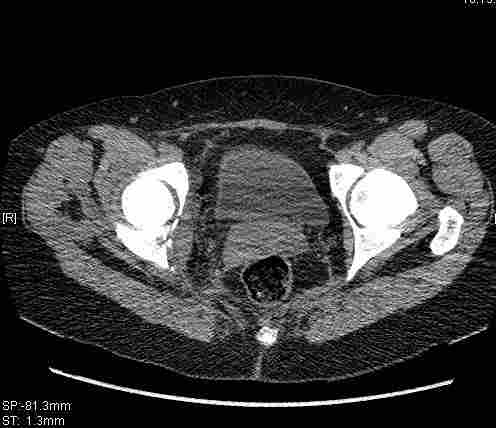

Удалось сегодня вывести пациентку в соседнюю больницу, где есть кт. Срезы сделаны только горизонтальные.

Приветствую,Антон.Рункова рядом нет,но после полученных данных КТ,обсуждали совместно.Итог обсуждения-развернутый ответ дать не получится,т.к.срезы выбраны не информативные.Если ориентироваться на данные 3D,то ,ИМХО,можно лечить на вытяжении.